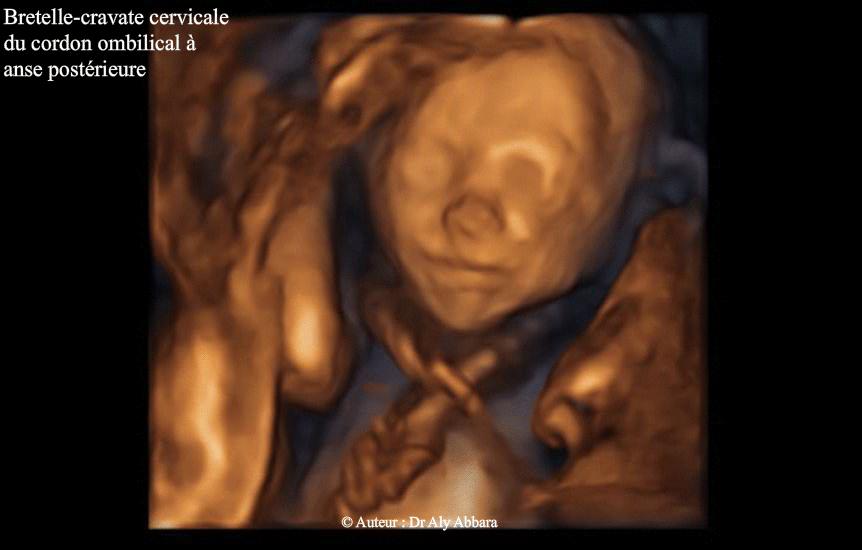

Bretelle funiculaire cervicale,- Images 3D

• Bretelle cervicale du cordon ombilical :

• Images échographiques en 2D, puis en 3D mettant en évidence la présence d'une bretelle funiculaire autour du cou fœtal :

• 1- Une bretelle-cravate à anse postérieur (images 2D et première image 3D)